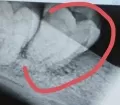

• Нужен осмотр полости рта и этого зуба, степени его подвижности, оценка Вашего прикуса, данные рентгеновских снимков. Лучше проконсультироваться с врачом-ортодонтом, который устанавливал брекет систему.

• Возможно, травмировался периодонт зуба, это связка удерживающая зуб в лунке, собственно, поэтому зуб и подвижен. Необходимо сделать рентгеновский снимок, проверить состояние периодонта.